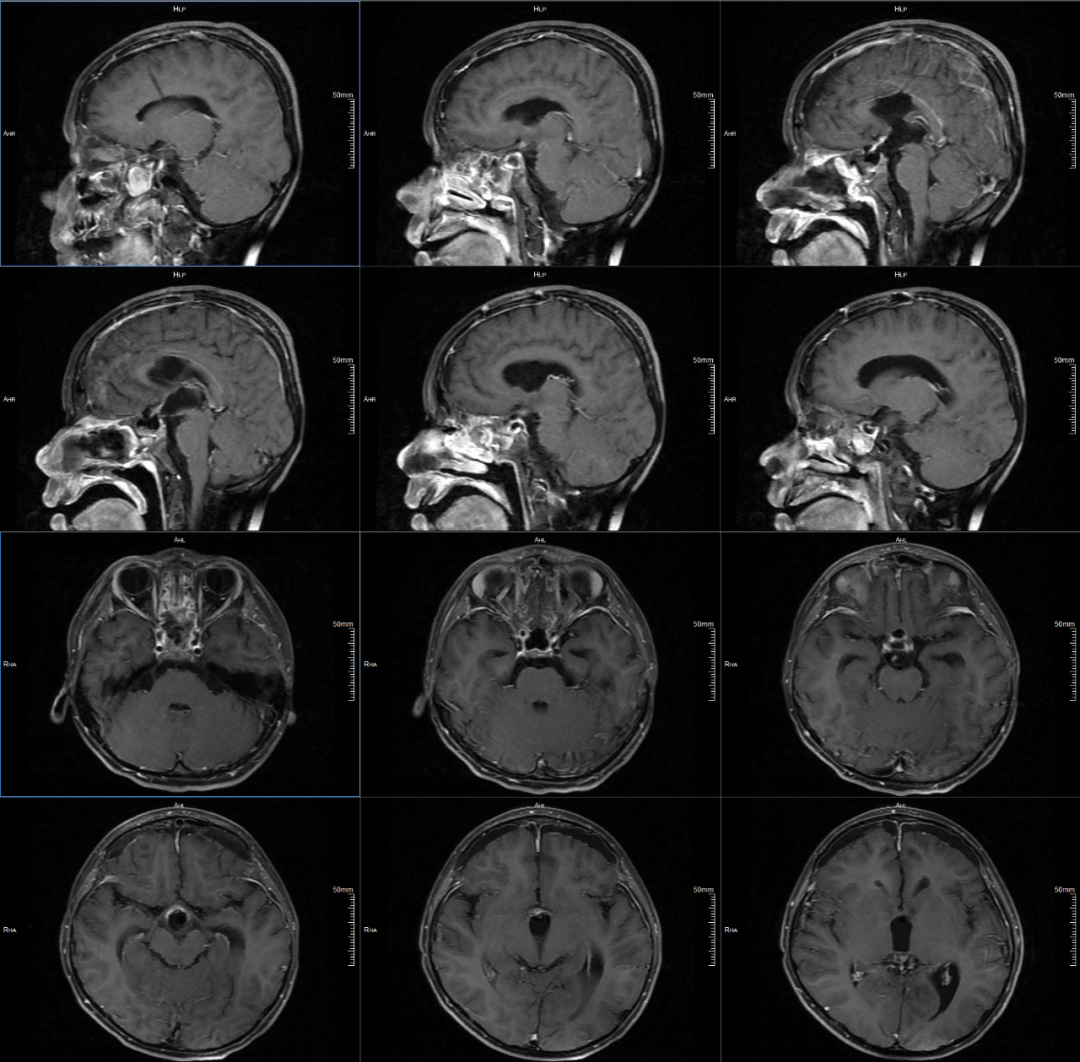

最终,历时八小时,纪文元医生在直径不足1.5厘米的狭小空间内,采用轴内分离切除的技术,小心翼翼将剩余肿瘤一点一点慢慢剥离下来,不仅没有损伤周围血管和神经,还保留了残存的垂体和垂体柄。“只残留约0.5毫米大小的薄层肿瘤。”纪文元医师解释,这部分残留肿瘤呈“指压状”陷入下丘脑,若强行剥离会损伤下丘脑,得不偿失,术后注意随访观察肿瘤是否会发生变化即可。

术后核磁共振影像图

“这已经是最完美的结果了。术后孩子的记忆力、视力一点都没有受到影响。”军军妈妈满意说。